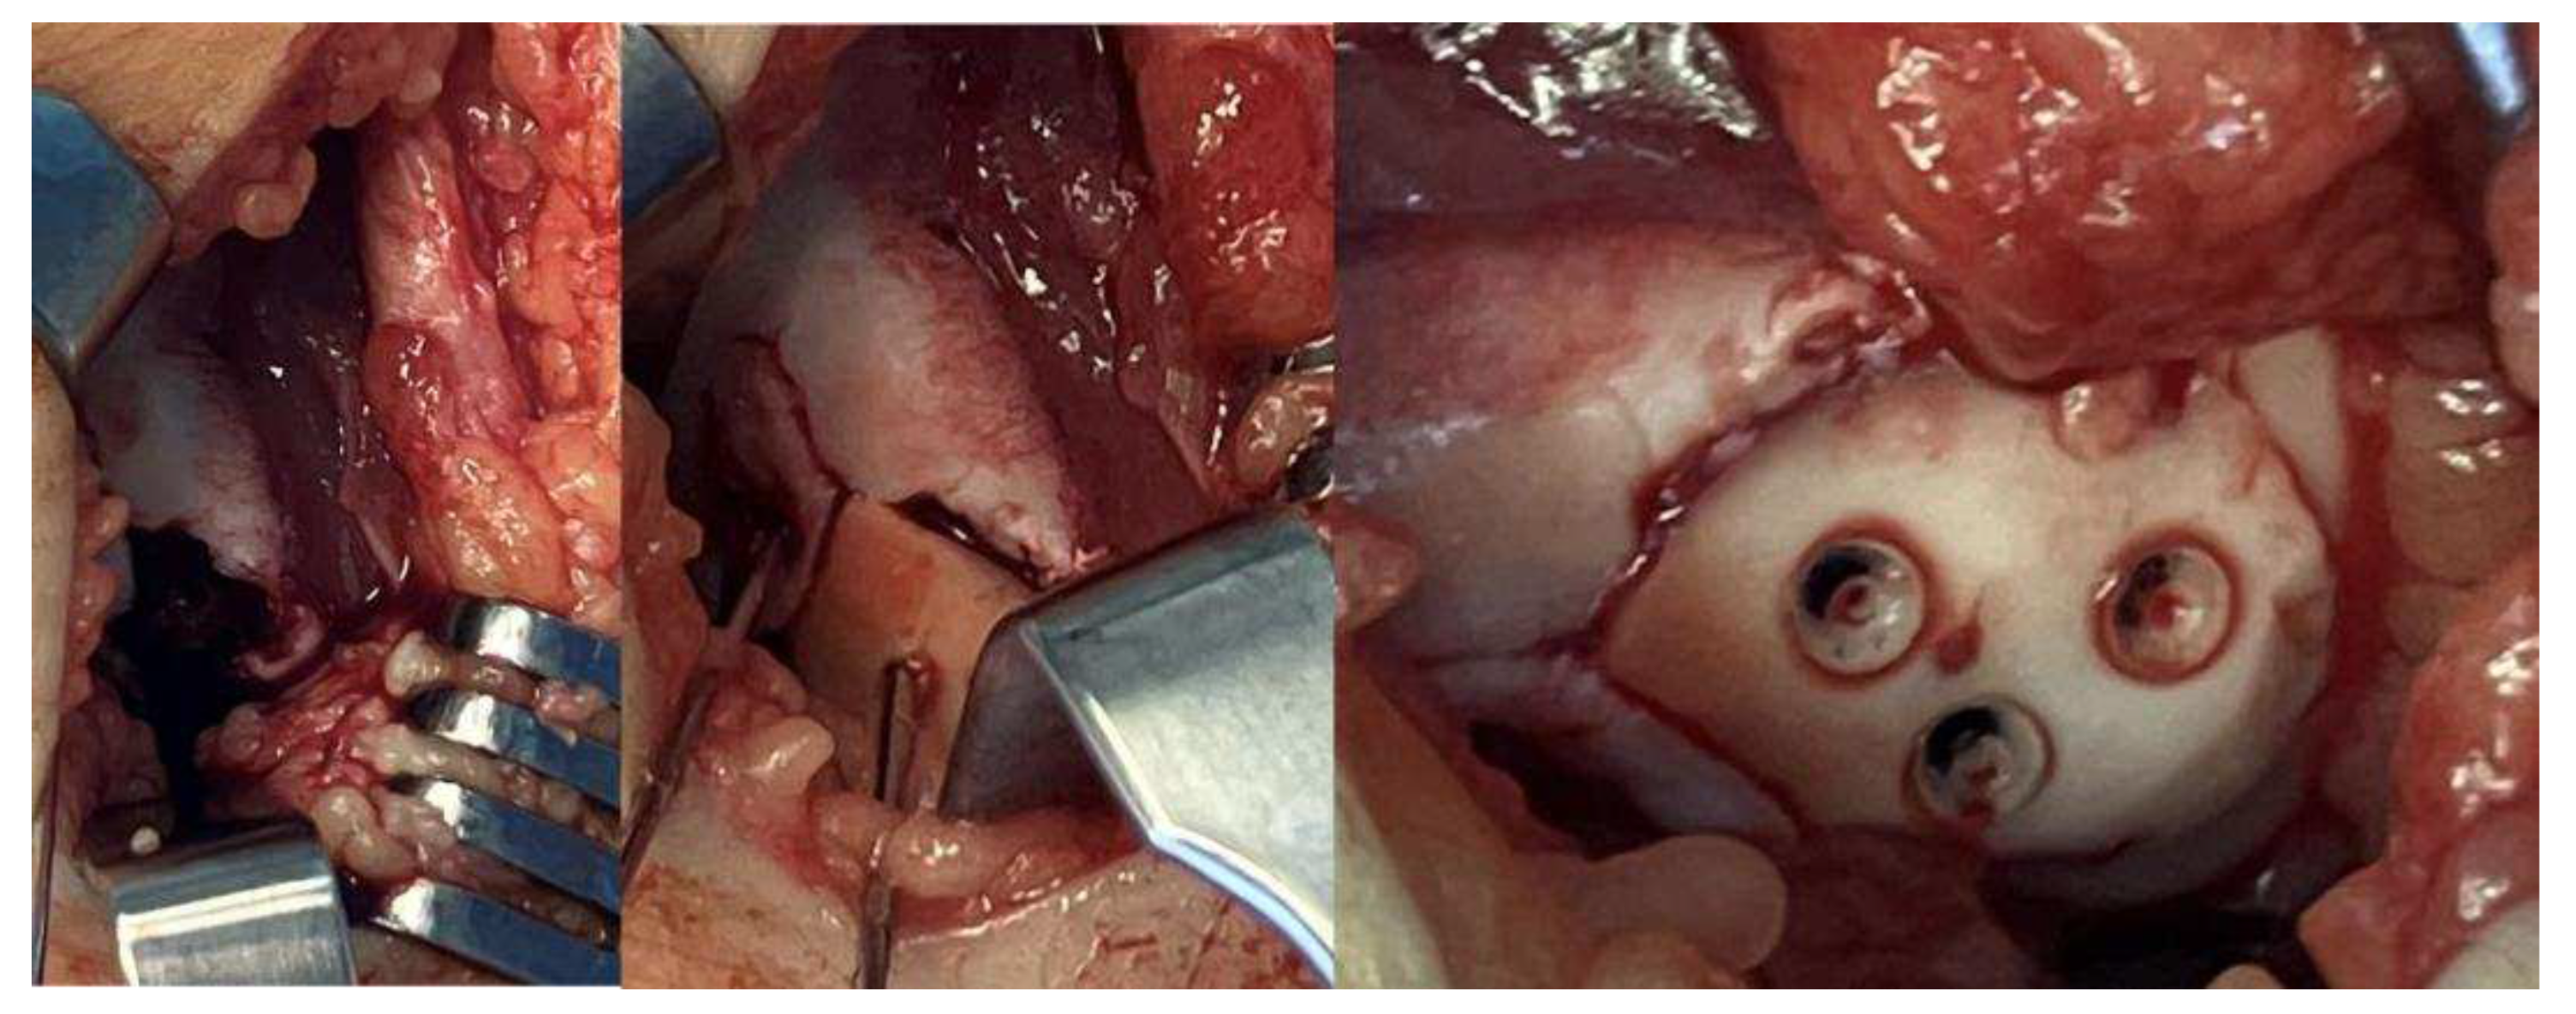

- Surgical Methods: